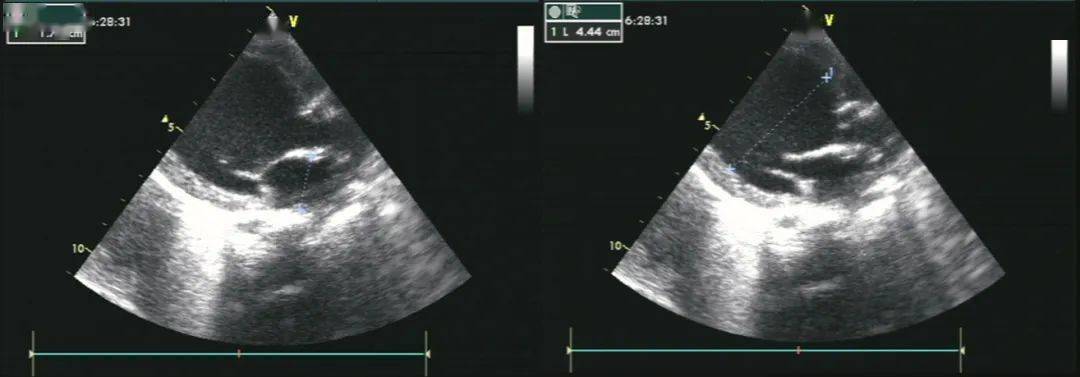

超声诊断为心内膜弹力纤维增生症,左心扩大并左心功能不全.